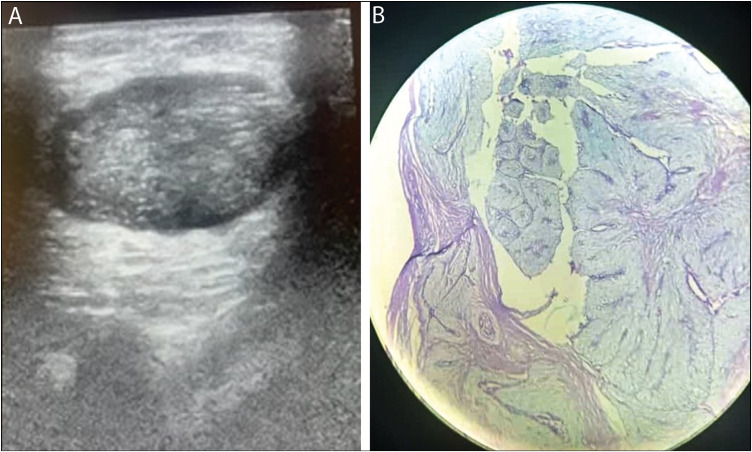

Background: Following recommended guidelines, palpable breast lumps in young women should be subjected to clinical-radiologic evaluation and tissue diagnosis where necessary. However, in our local practice, most benign breast lumps are also subjected to excision biopsy. Ultrasonography is the modality of choice in the evaluation of palpable breast lumps in young women.

Materials and methods: This was a prospective cross-sectional study of 87 adult females who had breast US and biopsy for palpable breast lumps in a tertiary healthcare center over a period of 10 months (July 2020-May 2021).

Results: The age range of the women was 18-39 years (mean 27.9 ± 7.09 years).Benign lesions were noted in 86.2% of patients. No malignancy was detected in women < 25 years. Ultrasonography had sensitivity, specificity, positive predictive value, negative predictive value, and accuracy of 100%, 93.4%, 70.6%, 100%, and 94.3%, respectively, in differentiating benign from malignant breast lumps following tissue diagnosis.

Conclusion: Ultrasonography and tissue biopsy are vital in the evaluation of breast lumps in women less than 40 years of age. Most (86.2%) of the lumps were benign, and no malignancy was detected in women < 25 years. The high accuracy of ultrasonography in distinguishing benign from malignant lesions suggests the need for conservative management of benign lumps in young women.